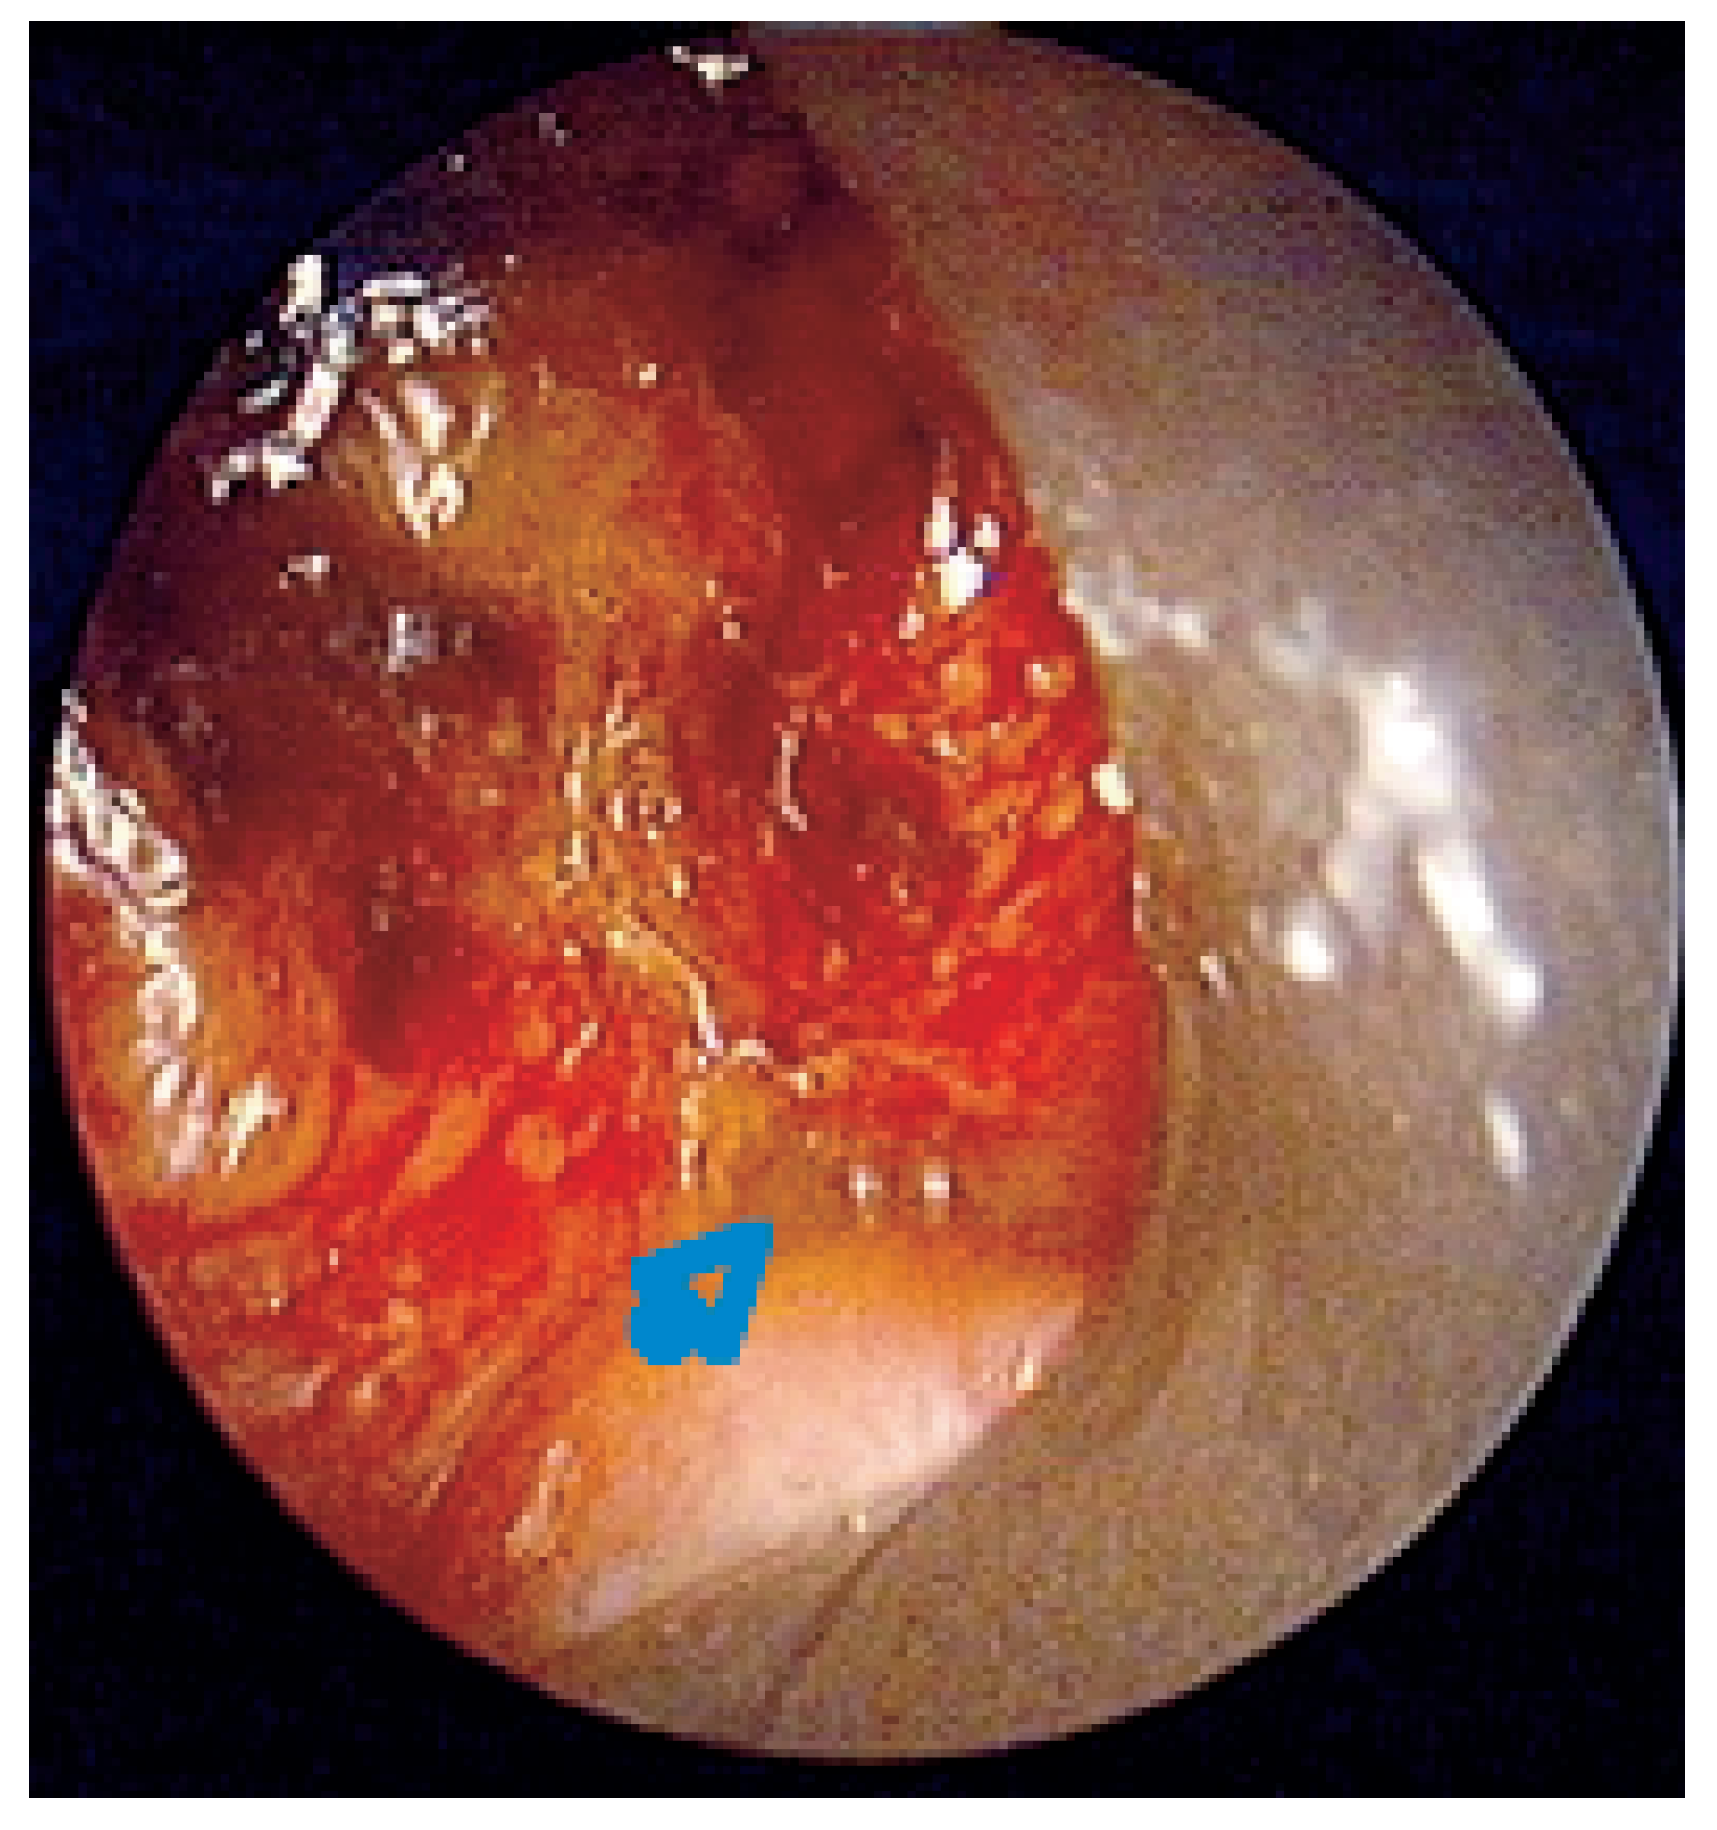

Abbildung 6. Überschichtung eines unbeschichteten Nitionol-Stents durch Granulationsgewebe.